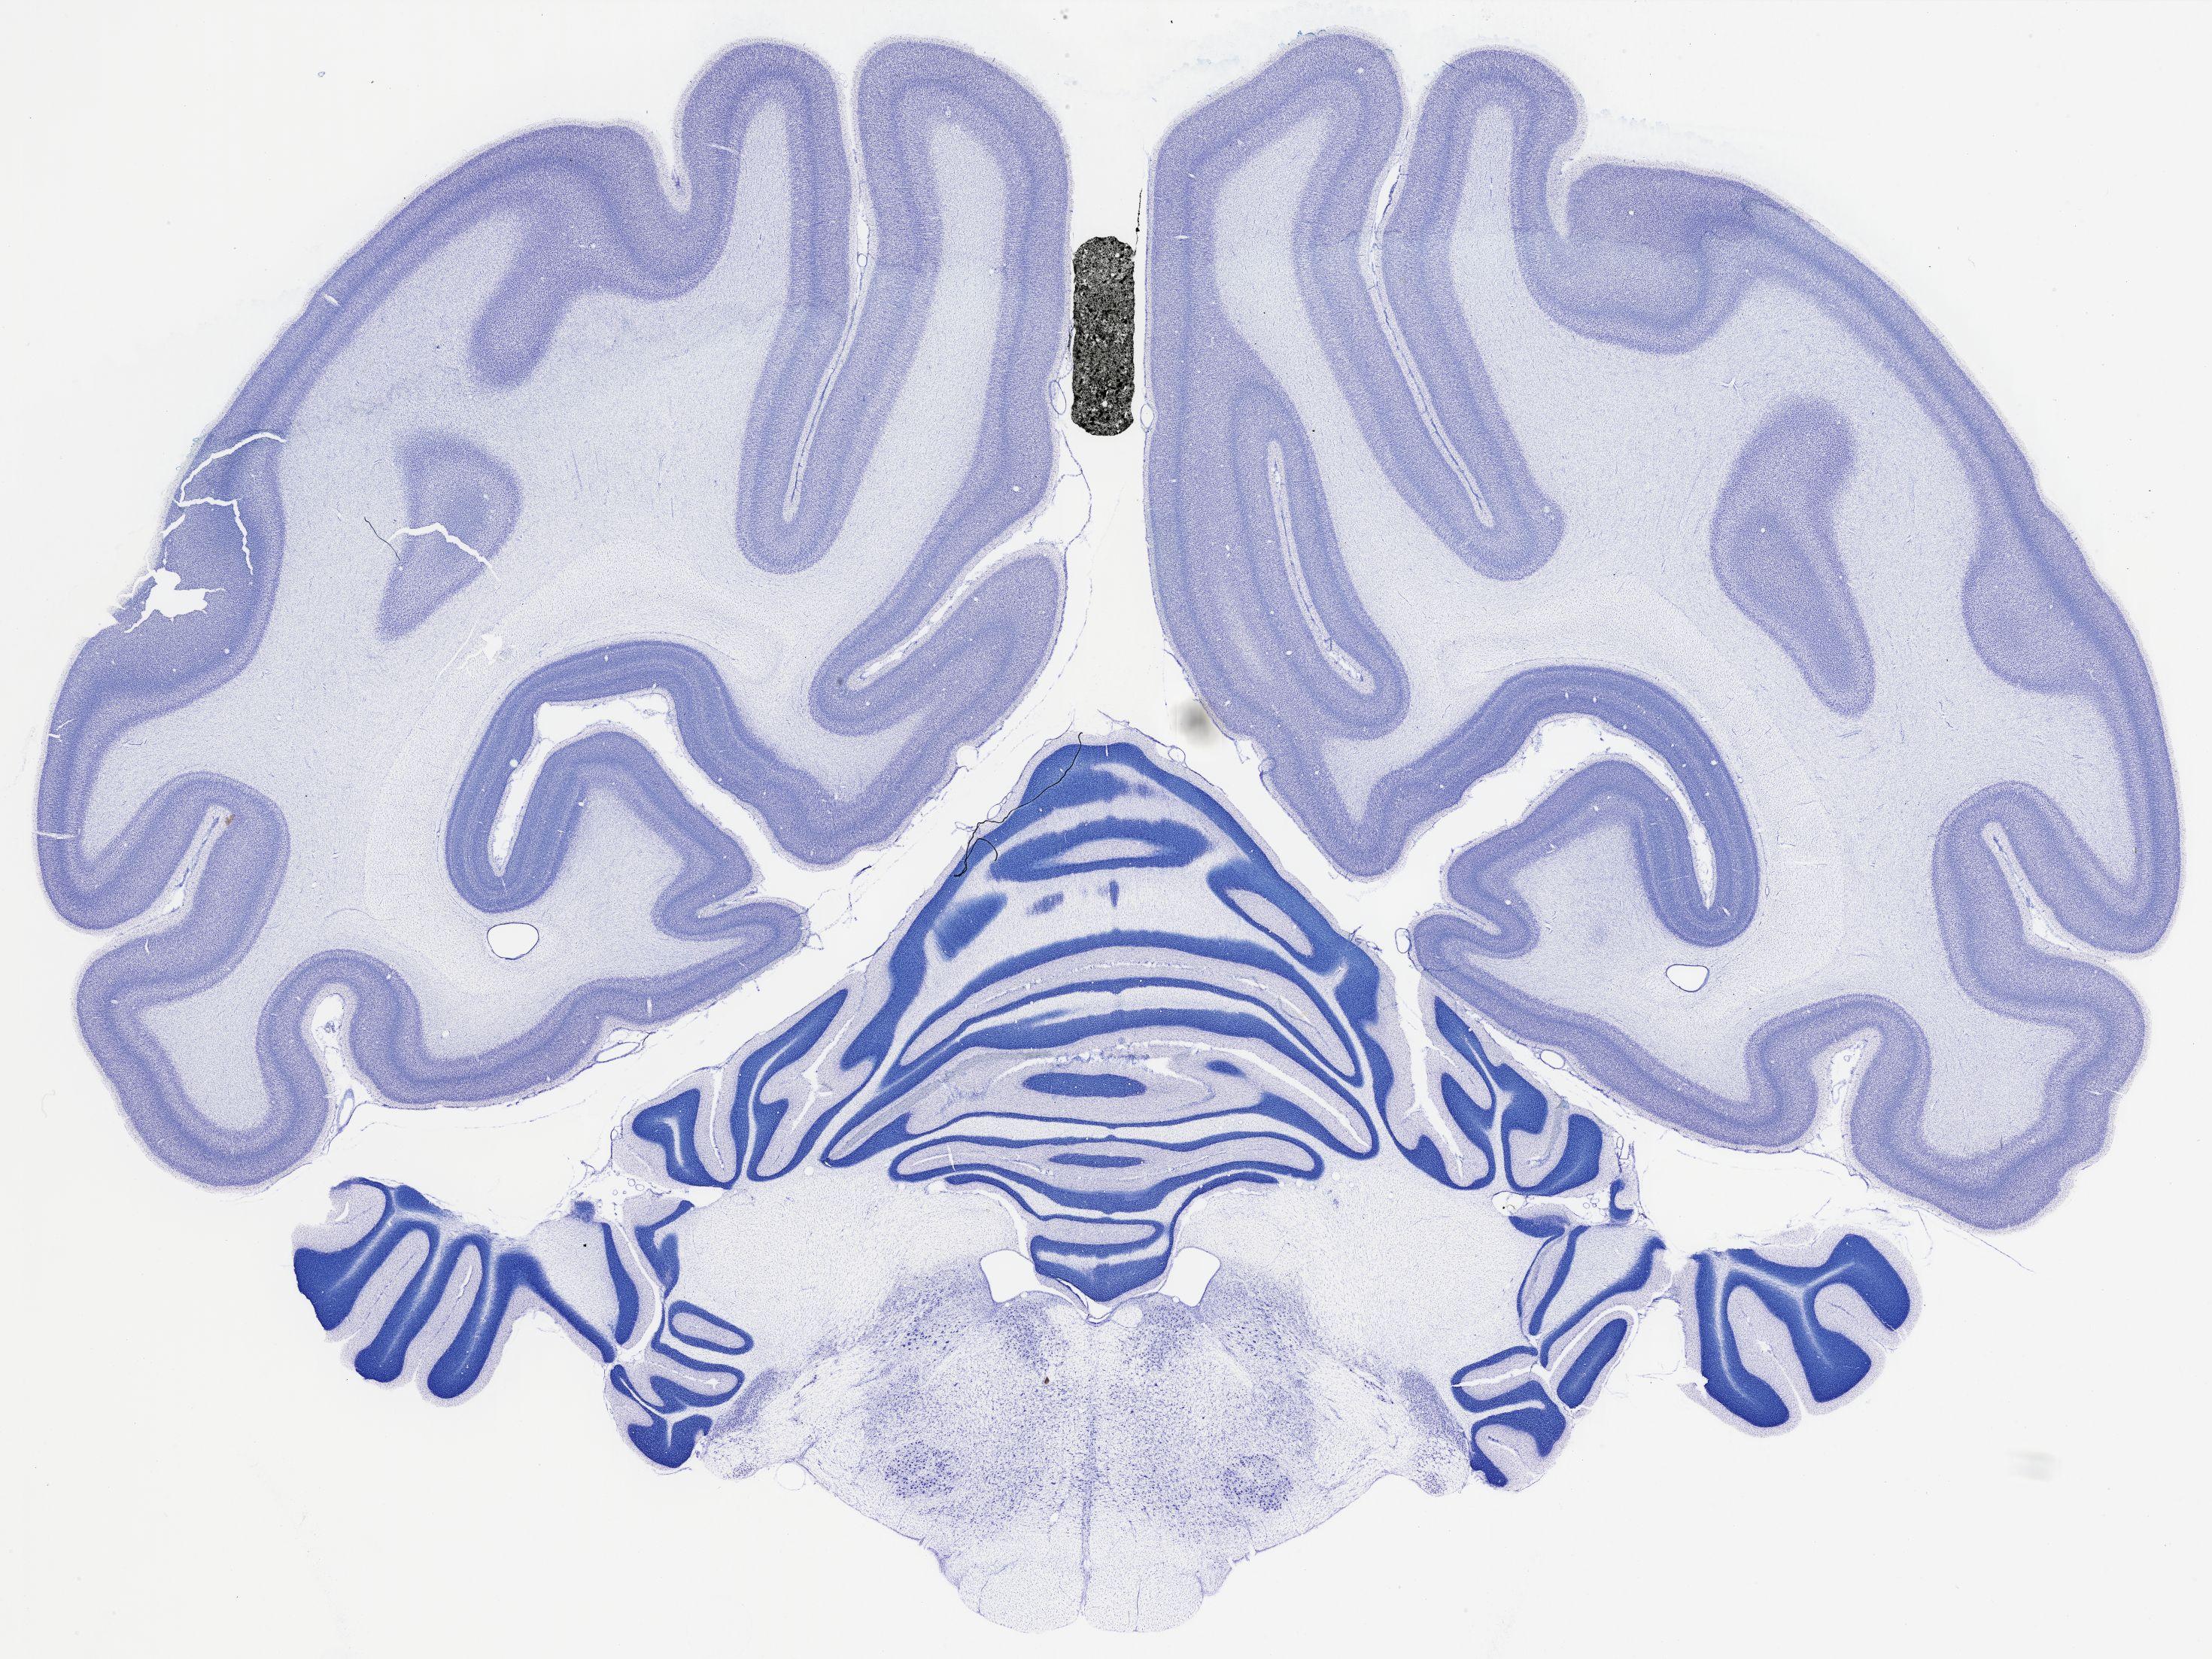

thumbnail

522